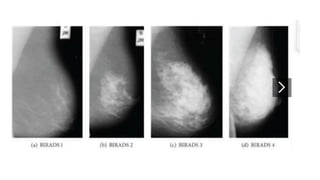

MAMOGRAFÍA

MAMOGRAFÍAS

https://www.bepink.mx/mastografia.html